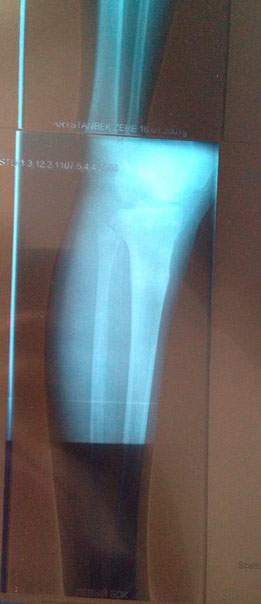

Рентген контроль в 81 день с момента снятия аппаратов.

Сращение железное, никаких ограничений! На физ-ру ходить можно! И ждём фото ножек девочки!